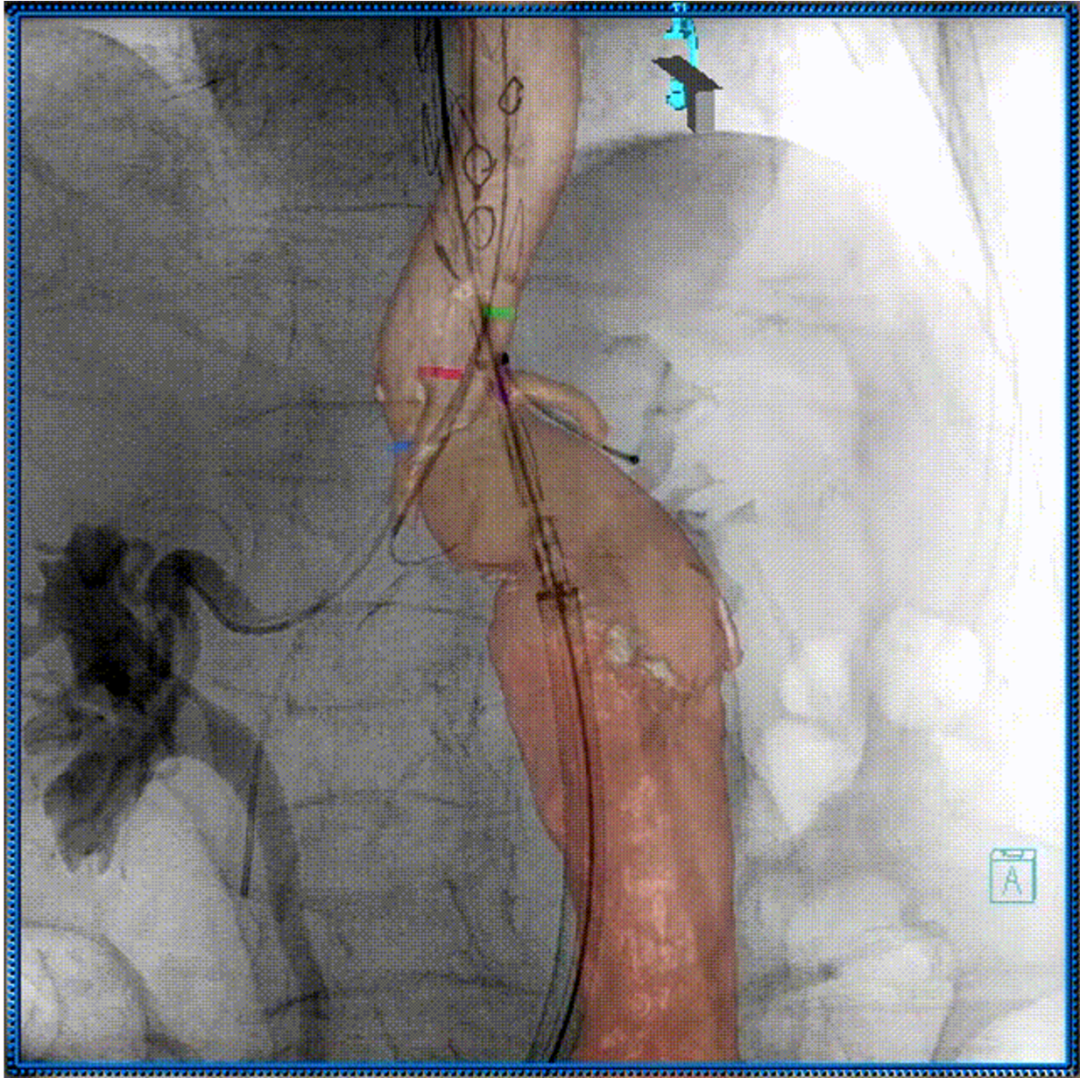

3D影像引导下完成窗口超选、置管及确认

肠系膜上动脉重建

左肾动脉重建

右肾动脉重建

四分支重建后造影,各分支血流通畅